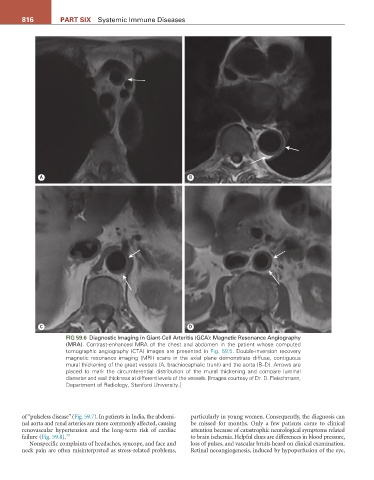

FIG 59.6 Diagnostic Imaging in Giant-Cell Arteritis (GCA): Magnetic Resonance Angiography

(MRA). Contrast-enhanced MRA of the chest and abdomen in the patient whose computed

tomographic angiography (CTA) images are presented in Fig. 59.5. Double-inversion recovery

magnetic resonance imaging (MRI) scans in the axial plane demonstrate diffuse, contiguous

mural thickening of the great vessels (A, brachiocephalic trunk) and the aorta (B–D). Arrows are

placed to mark the circumferential distribution of the mural thickening and compare luminal

diameter and wall thickness at different levels of the vessels. [Images courtesy of Dr. D. Fleischmann,

Department of Radiology, Stanford University.]